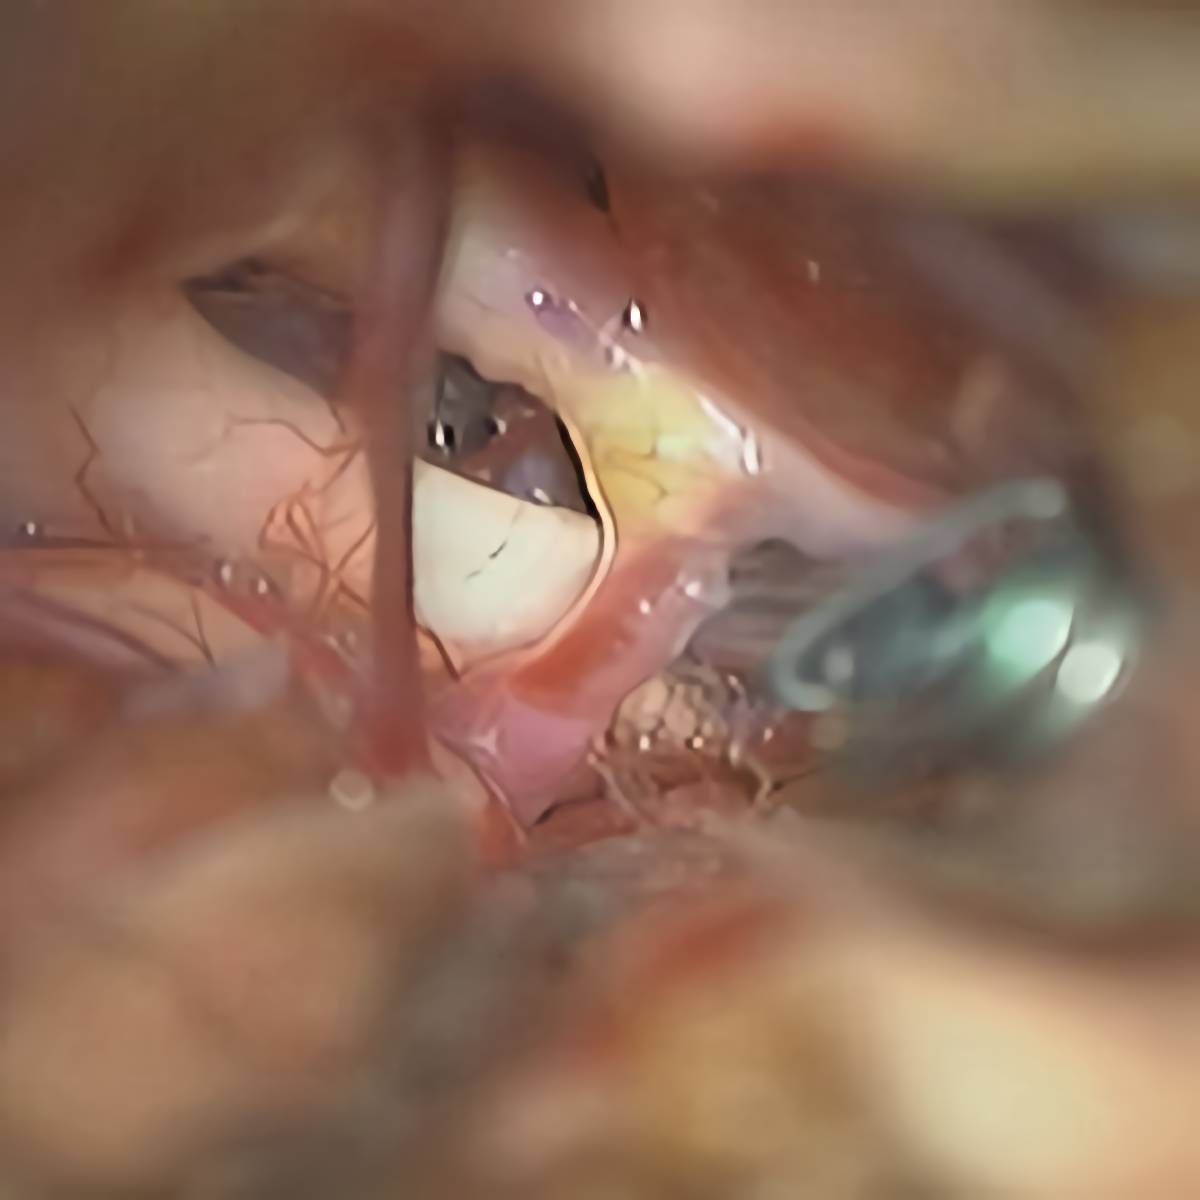

クリップ前

クリップ後

術後血管撮影

55

'18年4月

40代

左内頚動脈後交通動脈

分岐部動脈瘤

クリッピング術